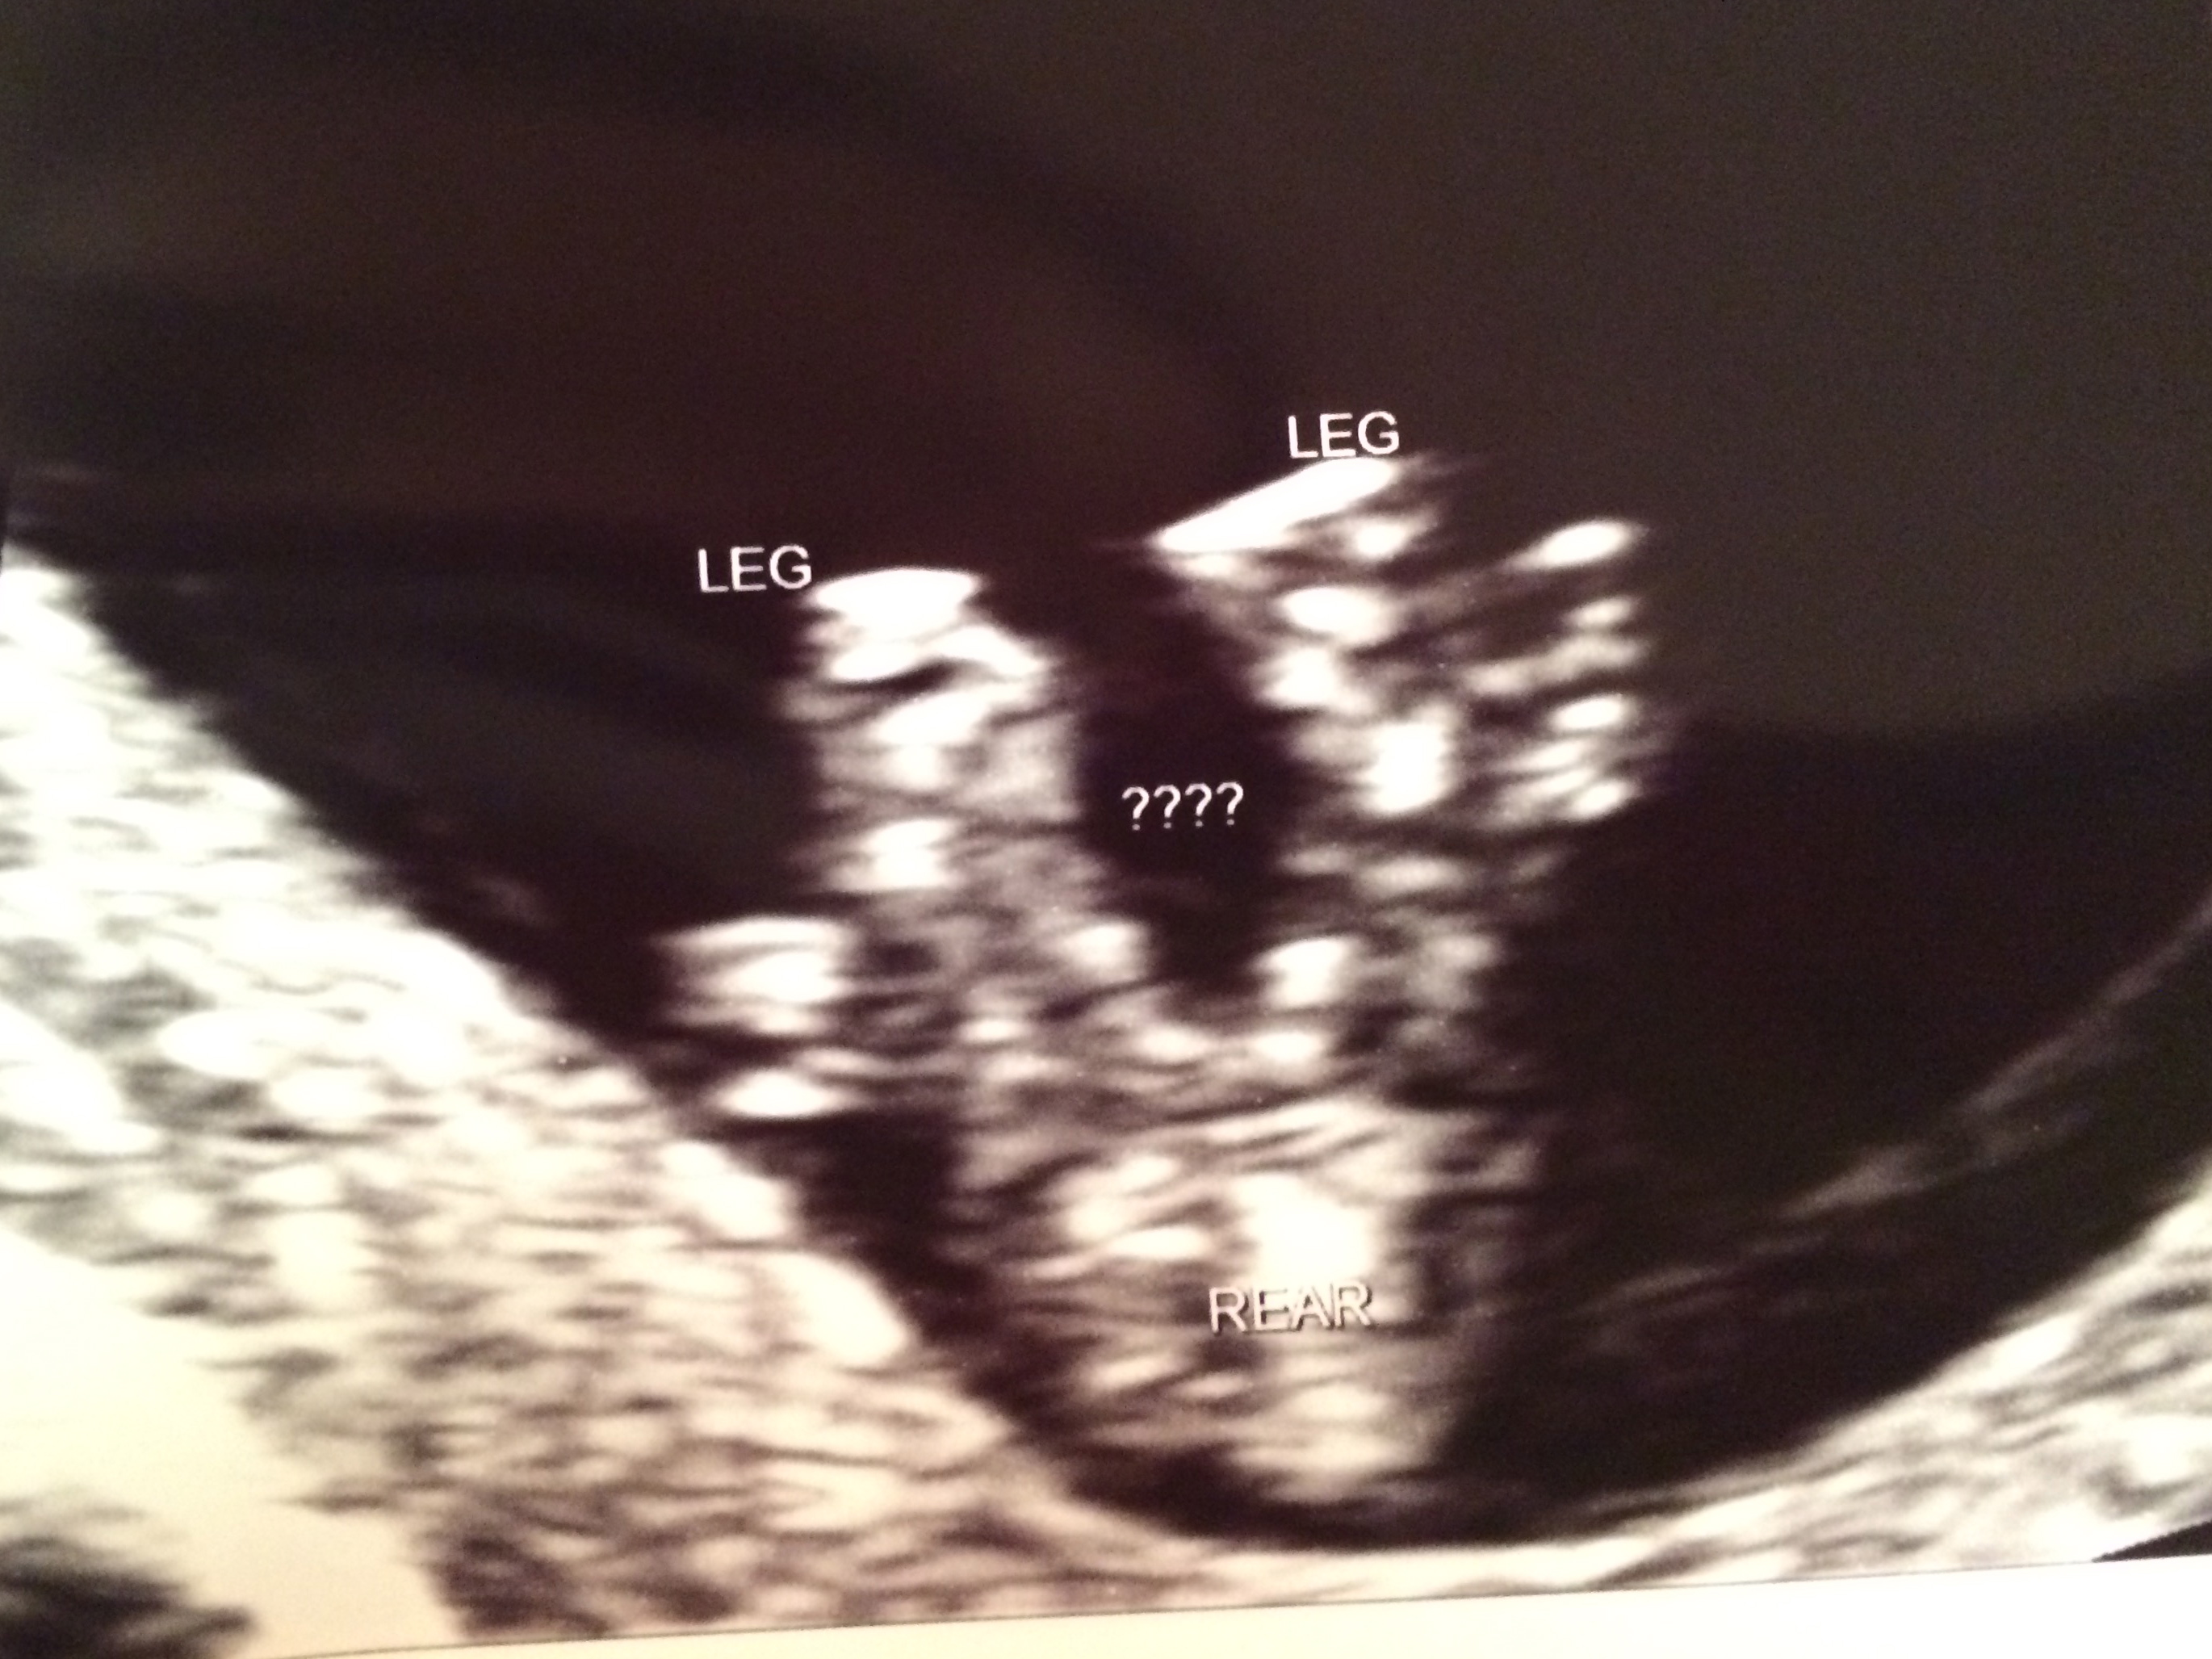

12 wk 1 day Nub and Potty Shots - Please guess Baby #4!

We had our NT scan today and our u/s tech took a guess. The baby measured 12 wk 1 day. This is our 4th baby. The same tech has been our tech every time and she always guesses at the NT scan. She guessed wrong with baby #1, couldn't see with baby #2, and guessed right with baby #3. She took a guess today and I'd like to see what y'all think and if it's in line with her guess. I'll wait to tell you what she said after I get some guesses :) We go back for another u/s at 16 weeks to confirm the sex.

Attachment 24665